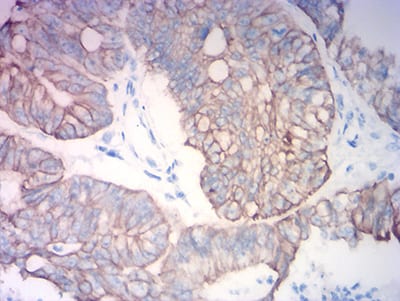

分类: 科研抗体货号: 31757别名: K18; CK-18; CYK18应用: WB,IHC,IF,FCM反应种属: Human

分类: 科研抗体货号: 31772别名: K18; CK-18; CYK18应用: WB,IHC,IF,FCM反应种属: Human